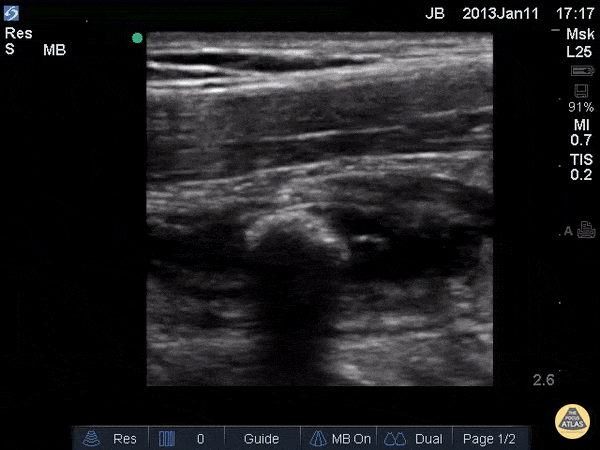

This images demonstrates a longitudinal view of an appendix that appears enlarged with edematous walls, containing a shadowing appendicolith, consistent with acute appendicitis. Justin Bowra MBBS, FACEM, CCPU Emergency Physician, RNSH et al.